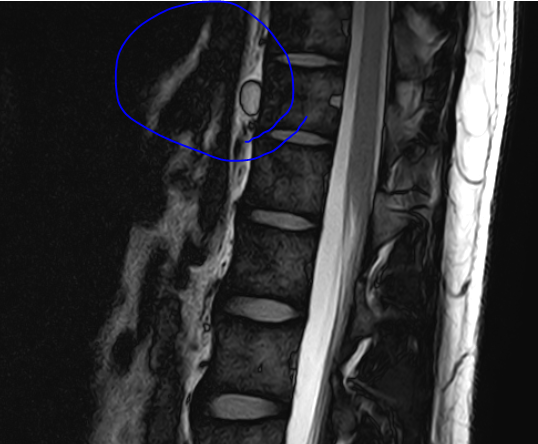

• 2번 째 사진

해당부분은 좀더 정확한 검사가필요하겠지만 낭종으로보이는데요 가까운 종합병원으로 내원해 관련된 검사를받아보시길 바랍니다

Mri에서 발견된 cyst는 척추에 발생한 낭종일 수 있어요 이런 낭종은 신경압박을 일으킬 수도 있기 때문에 정확한 진단과 추가 검사가 필요할 수 있습니다 정확한 진단과 치료 방법은 담당의사와 상의하는 것이 좋아요!